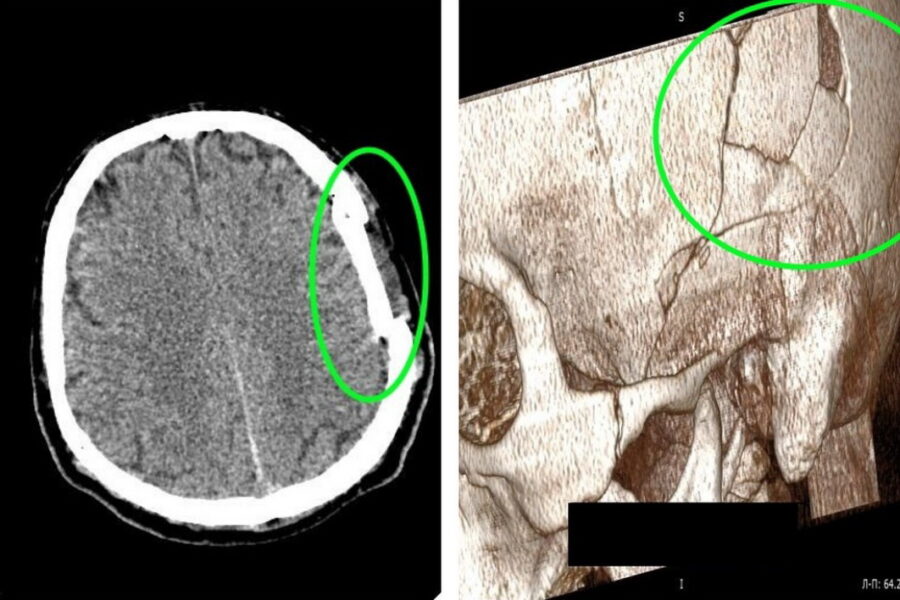

— Он получил тяжелую травму черепа с повреждением костей и смещением костных фрагментов в полость черепа. На снимке видно смещение костных фрагментов, сдавление головного мозга, — рассказал главврач Ярослав Фролов.